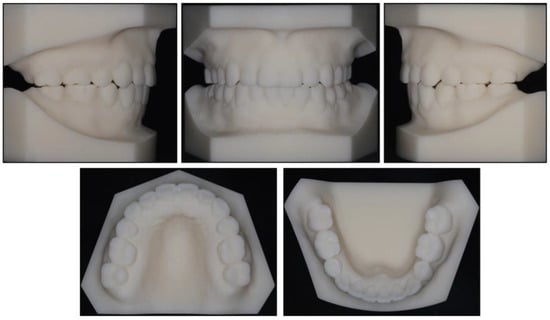

2.1. Diagnosis and Etiology